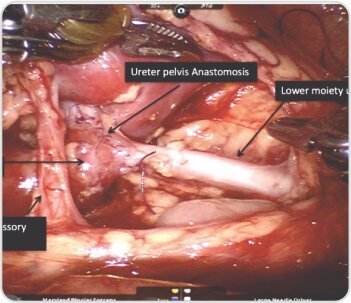

Robotic left-sided Uretero-Pyelostomy was done. Dilated upper moiety ureter was transected and anastomosed to lower moiety pelvis in end to side fashion. DJ stent was placed across the anastomosis into the upper moiety ureter. Post operative period was uneventful and the stent was removed after 6 weeks.